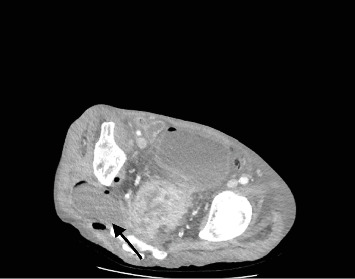

In this paper, we discuss the case of a late presentation, locally advanced rectal cancer that has perforated into the greater sciatic notch, presenting with symptoms of lower limb pain and recurrent falls. In this case, we discuss the complexities of diagnosing and managing atypical presentations of colorectal cancer.